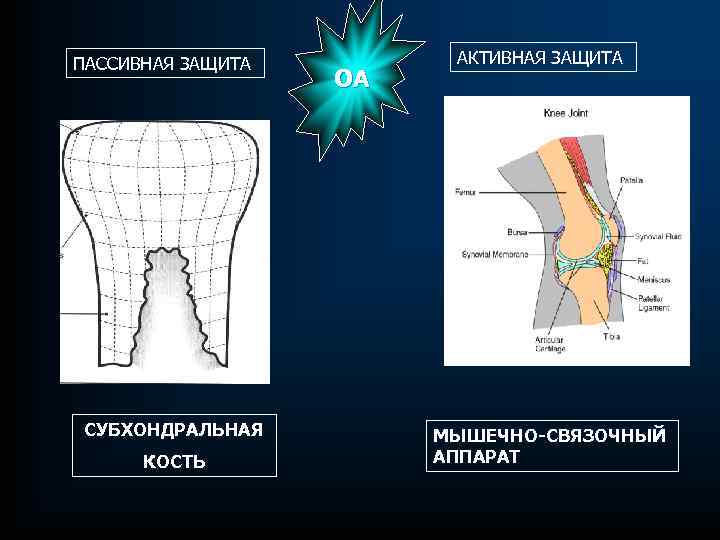

ПАССИВНАЯ ЗАЩИТА СУБХОНДРАЛЬНАЯ КОСТЬ ОА АКТИВНАЯ ЗАЩИТА МЫШЕЧНО-СВЯЗОЧНЫЙ АППАРАТ

ПАССИВНАЯ ЗАЩИТА СУБХОНДРАЛЬНАЯ КОСТЬ ОА АКТИВНАЯ ЗАЩИТА МЫШЕЧНО-СВЯЗОЧНЫЙ АППАРАТ